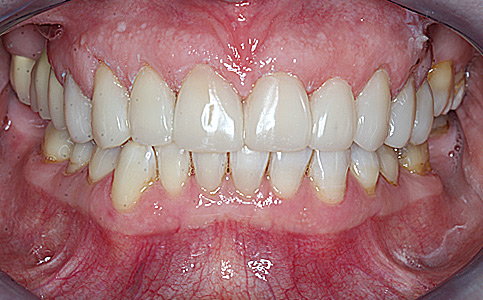

Pacjent zgłosił się do naszego Centrum stomatologii i Ortodoncji FRESHmed w Katowicach w celu poprawnia estetyki swojego uśmiechu. Po konsultacji i dokładnej diagnostyce, usunięto zęby dolne z powodu duzej ruchomości. Zęby zostały zastąpione 6 implantami zębowymi, na których odbudowano cały łuk zębowy dolny metodą All-on-6. Poprawę kształtu i koloru zębów górnych uzyskano poprzez zacementowanie koron pełnoceramicznych.